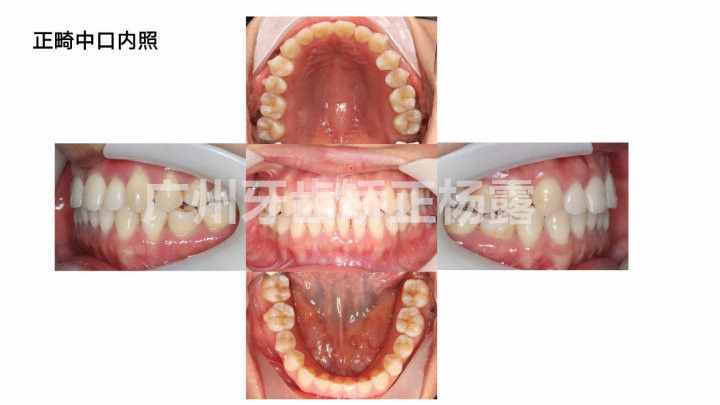

正畸前口内照

正畸中口内照